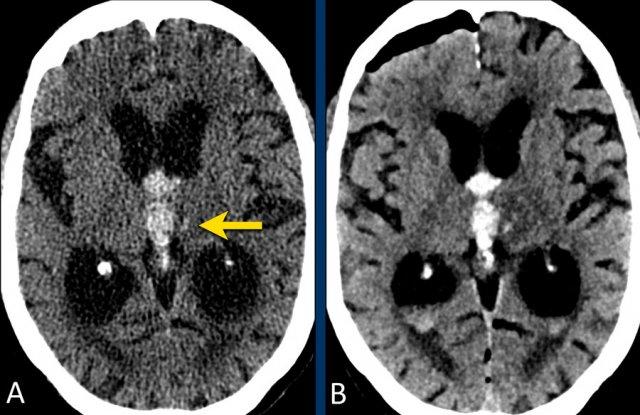

Đồi thị

Xuất huyết tại đồi thị thường gặp trong tăng huyết áp.

Bệnh nhân này nhập viện với não úng thủy do xuất huyết não thất (hình bên trái).

Lưu ý vùng tăng tỷ trọng rất nhỏ tại đồi thị trái, là điểm khởi phát của xuất huyết.

Theo dõi một ngày sau (hình bên phải).

Bệnh nhân được phẫu thuật đặt dẫn lưu não thất để điều trị não úng thủy.

Lưu ý đồi thị bên trái giảm tỷ trọng với ổ tăng tỷ trọng dai dẳng ở vị trí trong.